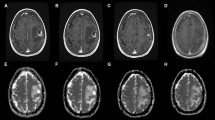

T1 weighted images as well as T2/FLAIR weighted images were co-registered to the corresponding ADC map sequence by using the software package statistical parametric mapping (SPM) [23]. Tumor segmentation was done by one person (LR) using a semi-automated active contour method (ITK-SNAP 2.0), which demonstrated excellent reliability and high efficiency of 3D segmentation [24]. The contrast-enhancing region in T1 weighted sequences, the non-enhancing T2 hyperintense region in T2/FLAIR weighted sequences, defined as peritumoral region (T2PZ) as well as the tumor- and edema-free gray and white matter compartment (GMWMC) were selected, representing three regions of interest. Contrast enhancing tumor regions and necrotic areas were excluded from the T2PZ. Within these three regions different ADC parameters were calculated using both MAtlab for first order and volumetric features and MaZda software package for textural features [25]. For a list of first order, volumetric and textural features please see Supplement 2. As studies have shown that the ADC may differ within the inner and outer border of the peritumoral region [17], we subdivided the peritumoral space into three adjacent ring-shaped spaces with an orthogonal diameter of each 3 mm, calculated the mean ADC of each ring Fig. 1.

Segmentation, registration of T1 contrast enhancing MR images as well as T2 images zo corresponding apparent diffusion coefficient (ADC) maps. We subdivided the peritumoral space into three adjacent ring-shaped spaces with an orthogonal diameter of each 3 mm and calculated the mean ADC of each ring as well as the ADC slope from the outer to the inner ring